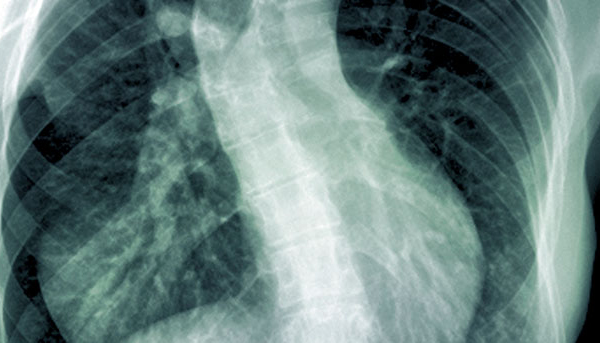

Condition / Treatment Scoliosis and Spinal Deformities